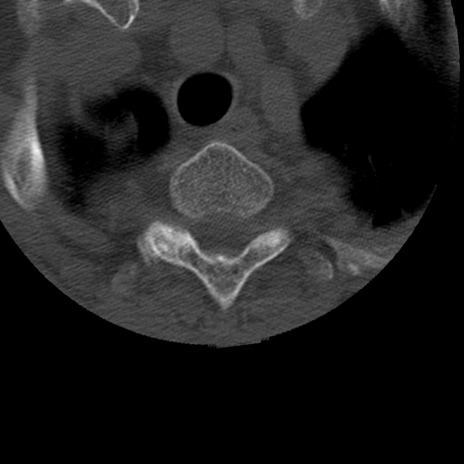

症例50 頚椎CT(横断像)

頚椎CT